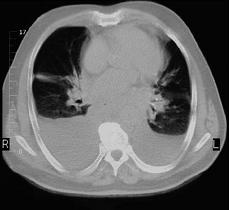

New England Journal of Medicine adlı tıp dergisinde yayınlanan bir rapora göre, her 3 tomografiden biri gereksiz ve tomografi kansere yol açabiliyor.

Kronik baş ağrısı ya da karın ağrısı şikayetiyle acil yardıma getirilen bir hasta, doktor muayenesinden geçmeden önce bilgisayarlı tomografiye girer. Şimdi bunun doğru bir yöntem olup olmadığı sorgulanıyor.

Doktor Brenner ve ekibi bilgisayarlı tomografiden yayılan radyasyonun önümüzdeki yıllarda tüm kanser vakalarının yüzde 2’sinden sorumlu olacağını öne sürüyor. Bilgisayarlı tomografi cihazları, klasik röntgendeki X ışınlarından çok daha fazla radyasyon içeriyor.